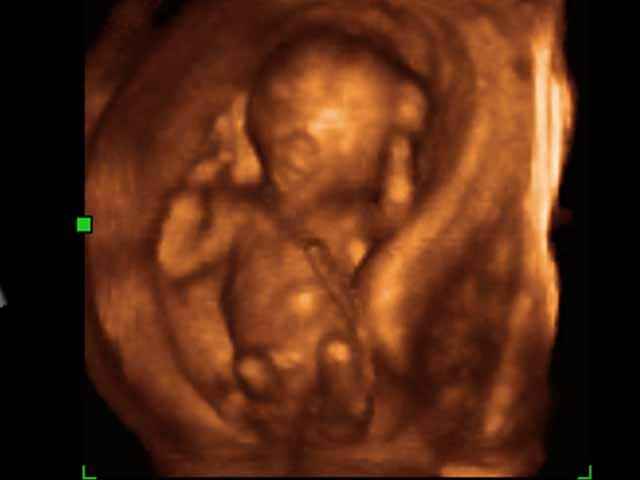

They are referring to pictures like the one below, which shows an unborn baby in the first trimester, the time when most abortions are performed

It is obvious that these images change hearts and minds, and pro-choice activists can no longer get away with arguing that the unborn baby is a clump of cells or blob of tissue. People can see the evidence with their own eyes. In fact, according to the article, 80 to 90 percent of the women who have sonograms at pregnancy centers choose to have their baby.